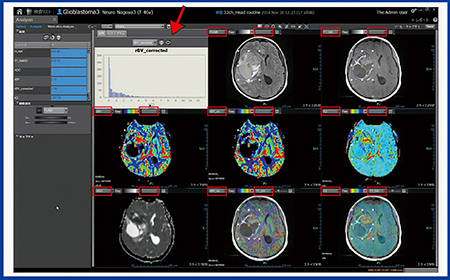

さらに,Olea Sphereの“Analysis”画面(図5)では,任意の2種類の画像(rBVとT1など)を選ぶだけで画像をフュージョンすることができる。さらに複数の画像を並べて表示できるため比較しやすく,同時にヒストグラム解析も表示できる。ROIは,領域ごとにワンタッチで設定することもでき,非常に有用な機能である。

図5 Analysis画面

□からプルダウンで画像を2種類選択すると自動でフュージョンされ,また各画像やマップにおけるROI内のヒストグラム(↓)も表示される。